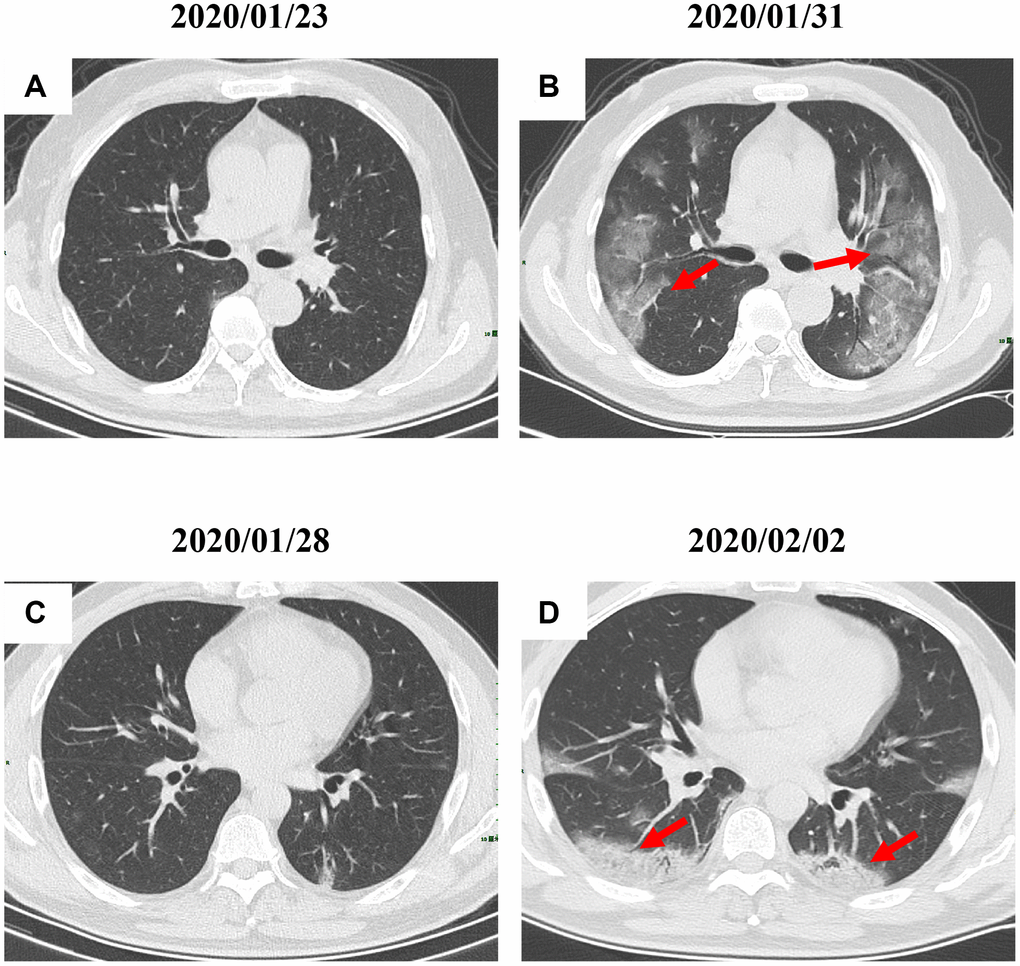

By Mar 23, 2020, 60 (60/66, 91%) patients had been discharged. 6 (6/66, 9%) patients were still in hospital, and two patients had died because of ARDS. Patient 1, 78-year-old man with hypertension, who died on day 15 after admission (Figure 1B). Patient 2, 47-year-old man with type 2 diabetes, whose CT scan presented rapid radiology progression (Figure 3A, 3B). The radiological change of COVID-19 pneumonia develops fast during the first seven days (Figure 3C, 3D). Some of patch lesion could be absorbed and change into reticular spline lesion (Figure 4A, 4B). Meanwhile, some patients achieved rapid recovery with significant improvement of CT sign (Figure 4C, 4D) and clinical symptoms. We also did some CT follow-up scans for few patients, which showed the aggravated progression of disease since admission and rapid recovery after treatment (Figures 5 and 6). Disappearance of lesions and significant improvement of clinical symptoms were observed in two patients (Figure 5: a 54-year-old male patient; Figure 6: a 54-year-old female patient).

Figure 3. Radiological worsen progression of two COVID-19 pneumonia patients. (A, B): Bilateral, large, and multiple ground-glass opacity was observed in a 47-year-old male patient with type 2 diabetes after 8 days since admission; (C, D) Consolidation accompanying air bronchogram were found in the bilateral lower lungs of a 29-year-old male patient after 5 days since admission. Typical lesions were marked with red arrows.